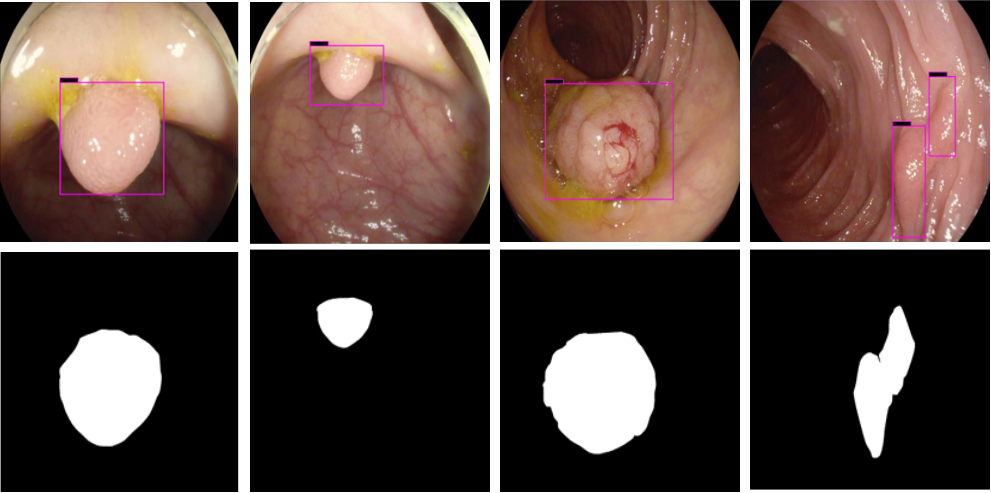

The results shown in Fig. 6 are generated using the proposed deep CNN model on the augmented data set. It can be observed that the proposed model shows better polyp detection performance. As illustrated in Fig. 6, polyps within a frame can be identified at multiple positions, and as noted above in this case, the TP for detection is considered to be 1. The proposed deep CNN model performed better than other benchmark results in terms of the performance metrics listed above, as shown in Table. 2 and Fig. 6.